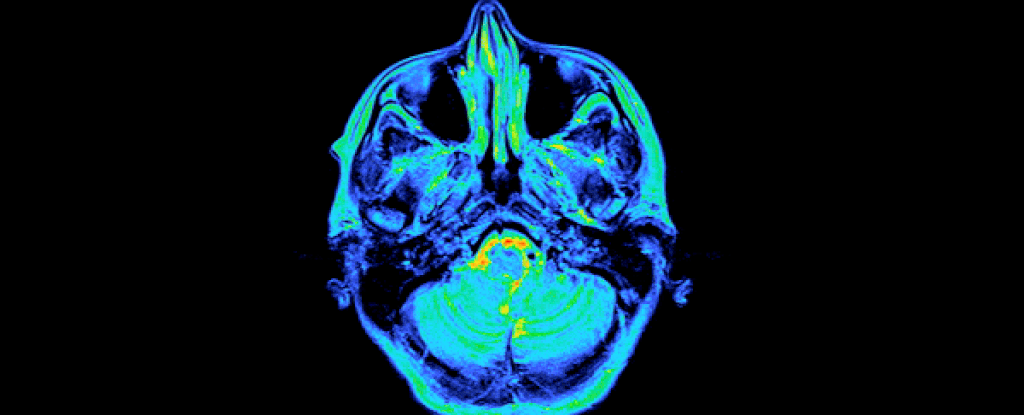

Neuroscientists in the US have now provided the first detailed map of the human brain across gestation.

“We were able to observe sweeping changes in gray matter volume, cortical thickness, white matter microstructure, and ventricle volume as it all unfolded week by week.”

During pregnancy, over 80 percent of the brain regions that neuroscientists examined showed reductions in gray matter of about 4 percent, on average, although everything returned to normal at the end of the pregnancy. That’s about the same magnitude of change observed during puberty, the authors say.